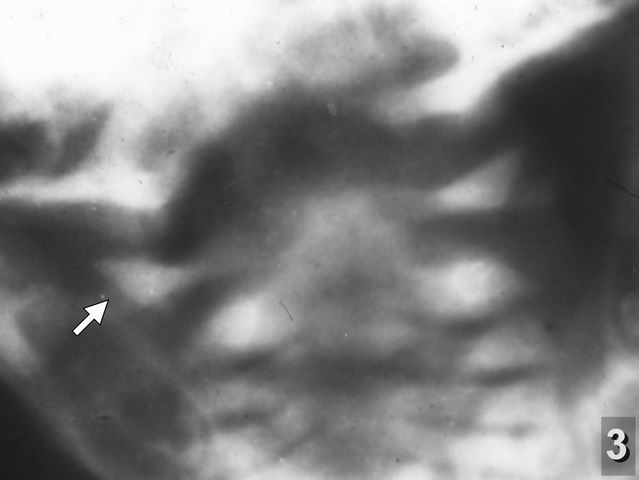

При одних и тех же повреждениях клиническая картина родовых травм шейного отдела может существенно различаться, что объясняется вариабильностью развития сосудов мозга у человека. Так, в моих наблюдениях при смещениях I шейного позвонка относительно II (рентгенограмма 1) чаще всего обнаруживались относительно негрубые неврологические симптомы, но были нередки случаи, когда они являлись причиной и острых нарушений кровообращения головного и спинного мозга. Однако наибольшую угрозу для жизни и здоровья детей представляли смещения атланта относительно затылочной кости (рентгенограмма 2) и переломы атланта (рентгенограммы 3 и 4), которые обычно приводили к тяжёлым и трагическим последствиям.

Отдаю себе отчёт в том, что эти рентгенограммы представляют интерес разве лишь для специалистов, имеющих непосредственное отношение к этой проблеме, но не для пользователей сайта "Живой Ангарск". Тем не менее, сознательно их публикую, чтобы показать диагностические возможности и важность обычной рентгенографии для выявления этой патологии. Рентгенологическое исследование шейного отдела позвоночника следует проводить детям не только при обнаружении явных клинических симптомов его поражений, но даже при подозрении на эти травмы: частота и тяжесть этих последствий несопоставимы с вредом рентгеновского облучения, получаемого младенцами при этих исследованиях. Признаки перенесённых родовых травм отчётливо обнаруживаются на рентгенограммах не только у детей грудного возраста, но и на последующих этапах их развития (рентгенограммы 5 и 6).

![]()

o" width="210" height="158" alt="Рентгенограмма 3" align="left" />Рентгенограмма 3 реб. К. 23 дня. Выраженное смещение правой боковой массы атланта относительно зубовидного отростка и суставной поверхности II шейного позвонка.